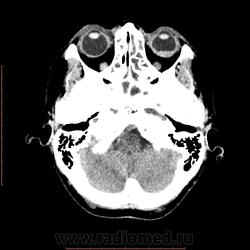

КТ орбит. Образование левого глазного яблока

Женщина 57 лет обратилась с жалобами на снижение зрения левого глаза. На УЗИ объемное образование левого глаза. Написал DDs меланома, ретинобластома.

Меланома - да, надо исключать. (наиболеее вероятно).

Рентинобластома - крайне маловероятна (после 5-ти лет эта опухоль практически не встречается).

Я тоже склоняюсь больше в сторону меланомы. Ретинобластома врожденная опухоль, в 90% случаев диагностируется как вы и сказали до 5 лет, у взрослых встречается редко и в 95% содержит обызвествления, но в дифф.ряд указал на всякий случай.